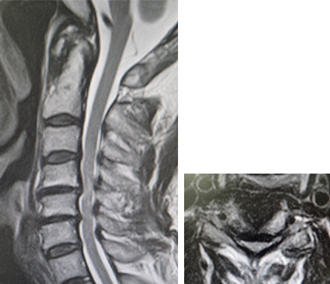

頚椎症性脊髄症・神経根症・頚椎椎間板ヘルニア

どんな病気?

せぼね(脊椎)は7個の頚椎、12個の胸椎、5個の腰椎と仙椎から構成されます。腰椎は主に5つの骨と、間にあるクッションのような椎間板、また神経組織が通っている脊柱管から成り立っています。頚部の神経組織は、脊髄と枝分かれする神経根から構成されています。頚椎症性脊髄症は、骨の変形や椎間板の膨隆、あるいは不安定性などにより、頚椎の脊柱管の狭小化が生じることで頚髄が圧迫される病気です。脊柱管が比較的狭い日本人は欧米人に比べて発症しやすい特徴があります。また、頚椎症性神経根症は椎間板の膨隆や骨棘(骨のトゲ)によって神経根が圧迫される病気です。

症状

局所の症状として、頚部や背部の痛み、また肩こりなどの症状が出やすいです。脊髄が障害されると、手指の巧緻運動障害(箸が持ちづらい、字が書きづらい、ボタンが上手くはめられない)、痙性歩行(ふらつき・つまずきやすい・歩行がぎこちない)、膀胱直腸障害(頻尿・残尿感)などの症状が生じます。神経根が障害された場合には、どちらか一方の腕や肩甲骨の裏側に放散する痛みやしびれ、力が入りにくいといった症状が生じます。

検査方法

せぼねの変形や椎間板の傷み具合、すべりや不安定性の有無、脊髄の圧迫の程度、またせぼね全体のバランスなどを見るためにX線検査やCT検査、MRI検査などを行います。進行例では脊柱管の狭さをより詳しく評価するために入院して脊髄造影検査を行う場合があります。どの神経が痛みの原因となっているかを明らかにするため、あるいは除痛目的に神経根に直接麻酔薬を注入する選択的神経根ブロックを行う場合もあります。成人期では血管性のしびれがないか評価するために両手足の血圧を測ったり、骨粗鬆症の有無を評価するために骨密度検査を行うこともあります。

治療方法

頚部痛などの局所症状に対しては、鎮痛薬やビタミン製剤などの内服、カラー、リハビリテーションなどの保存治療で経過をみます。保存治療で十分な効果が得られない場合、あるいは手足の力が入りづらい(麻痺)、歩行が不安定、また排尿や排便に障害(膀胱直腸障害)がある場合などには手術治療を考慮します。神経根症では頑強な疼痛の持続や、麻痺が進行性であれば手術治療を考慮します。重度の脊髄障害は、不可逆的になり回復が困難となることがあるため、早急な外科的治療を要することがあります。

頚椎症性脊髄症・神経根症・頚椎椎間板ヘルニアに対する低侵襲手術には以下の種類があります。